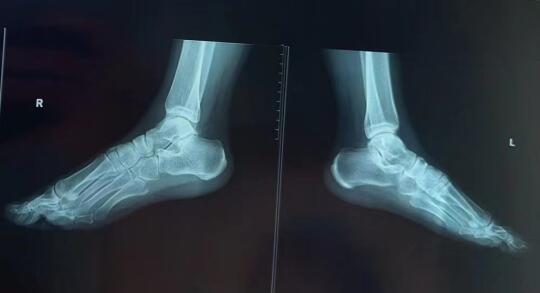

阿基米德说给我一个支点我可以撬动整个地球 而对于全身骨架来讲足结构就是他的支点 这次的案例是来自安徽的女生 因为崴脚后做手术后面做康复用了定制鞋垫 因为鞋垫定制数据没有量好 导致穿了一个月后整个下肢力线紊乱 骨盆偏歪 左侧大转子向外顶 右侧膝关节胫骨内侧不舒服 脚踝总是觉得内侧踩不下 跟骨向内翻 大脚趾踩不住力 小脚趾挤压 坐着的时候这个足内翻的力向上顶的膝盖不舒服 并且右侧腹股沟紧张 股骨头顶耻骨支很不舒服 严重时候右侧下肢皮肤发暗 子宫下垂 炎症 甚至出现便血 真的是 力断于脚 阻断于膝 而散于骨盆 更沉于全身 全身必然紊乱 身心则难安 心神不宁 一年多无法正常工作 最先找到我的学生调整 有所改善 但是感觉还差点意思 后来在平台上刷到我约个案 刚开始调大脚趾 然后再调内侧楔骨与第一跖骨 感觉内侧开始能踩上点力 又调整外侧楔骨还有骰骨 感觉外侧又稳了一些 但是坐着的时候 还是觉得膝盖被顶得难受 股骨头还是觉得顶耻骨难过 又调了跟骨内翻角度 踩得更稳 直到我又把她外旋的胫骨调内旋 这时候她才觉得膝盖好受并且股骨头顶耻骨的力更弱了 后面又调舟骨与骰骨后脚更稳了 跟骨是足结构的老大 但是这个老大受胫骨的牵制比较大骨盆 开胯 脚踝灵活性 膝关节稳定 脚踝疼 瑜伽 崴脚